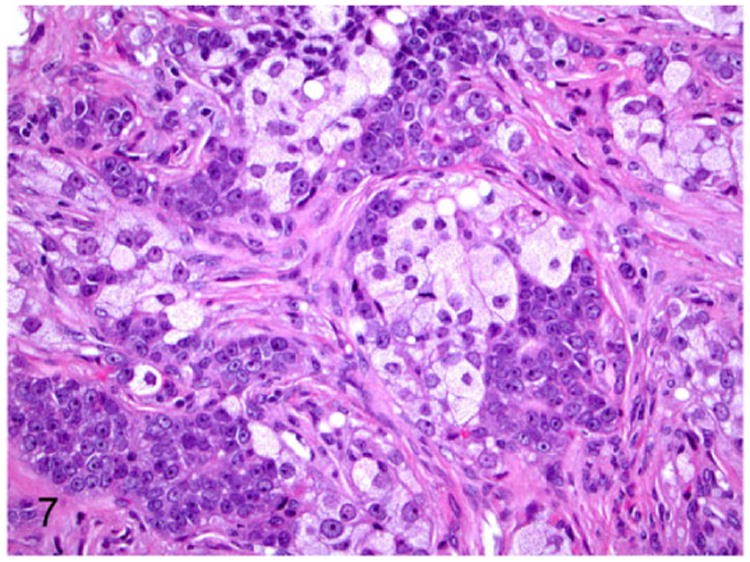

Adrenocortical carcinomas are large neoplasms (Fig. 3) with histological features closely resembling that of adenomas.41 In the carcinomas, the well-differentiated adrenocortical cells with intracytoplasmic vacuoles and angular proliferating cells are supported by fibrous connective tissue stroma (Fig. 7). Cellular atypia such as large nuclei, prominent nucleoli, anisocytosis, and anisokaryosis are not considered to be features of malignancy.4,41 However, mitotic figures greater than 1 per 10 HPF, metastasis to different organs, invasion of blood vessels, and necrotic foci are generally considered as features of malignancy in adrenocortical carcinoma.41

Figure 7.

Proliferative lesions of the adrenal gland, ferret. Adrenocortical carcinoma. The neoplasm is composed of clear cells with pale vacuolated cytoplasm and polygonal cells supported by fibrous connective tissue stroma. Hematoxylin and eosin (HE).